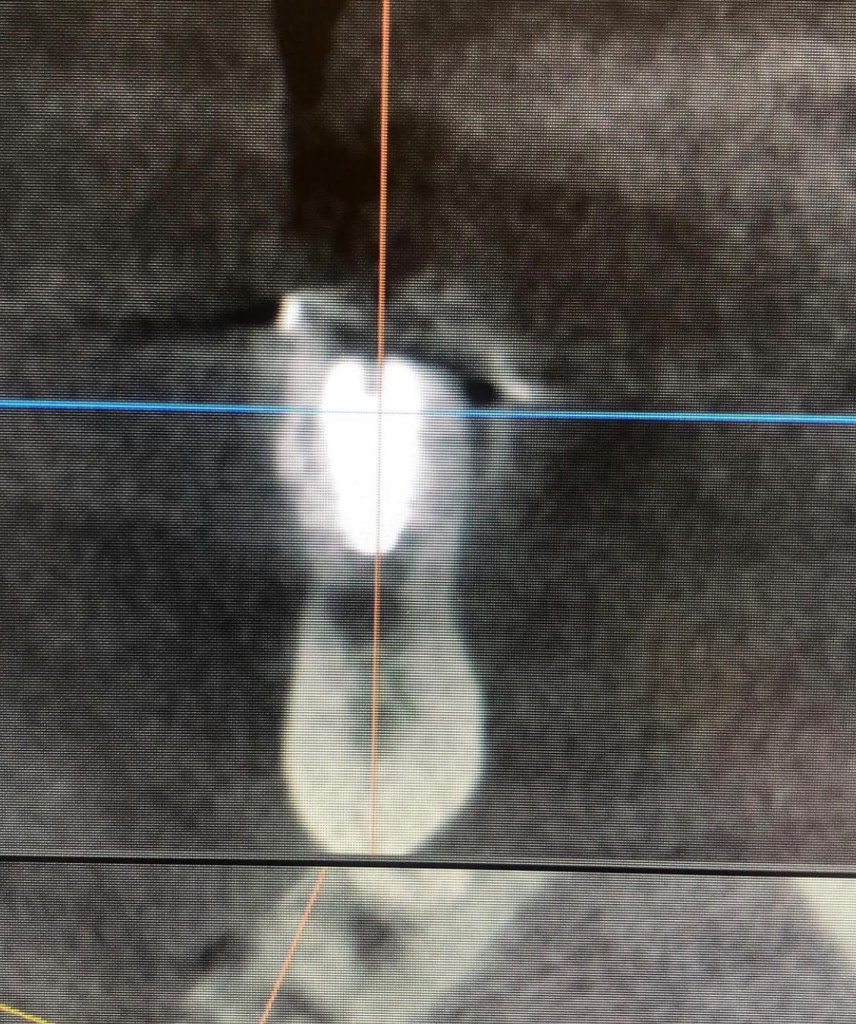

- Цифровое планирование позиций новых имплантатов AnyRidge

- Срезы КТ